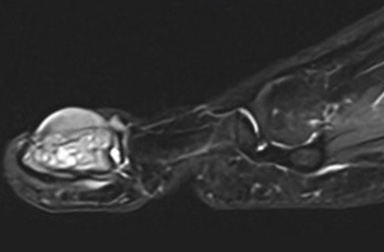

Ewing sarcoma of distal phalanx of the great toe in a 10-year-old boy: case report and review of the literature

Peeters S., Van Laethem A., Sciot R., Renard M., Labarque V., Vanden Bempt I., Verhamme B.

pp. 207-12